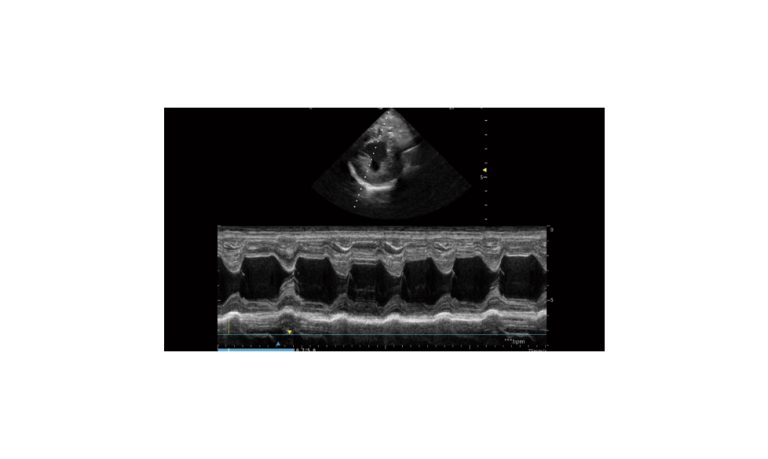

SonoScape Pro Pet E11

Smart Imaging

Introducing the first portable ultrasound with the C-Field+TM platform, redefining diagnostic imaging. Designed for veterinarians, it delivers unmatched clarity, ultra-fast processing, and seamless adaptability for all species. Experience Smart Imaging, Heartfelt Care—anywhere.

Equipped with cutting-edge veterinary software and optimized workflows, it embodies our commitment to Smart Imaging, Heartfelt Care – Wherever Their Journey Leads, with unparalleled performance and adaptability, this innovative system empowers veterinarians to provide exceptional care across all diagnostic applications,